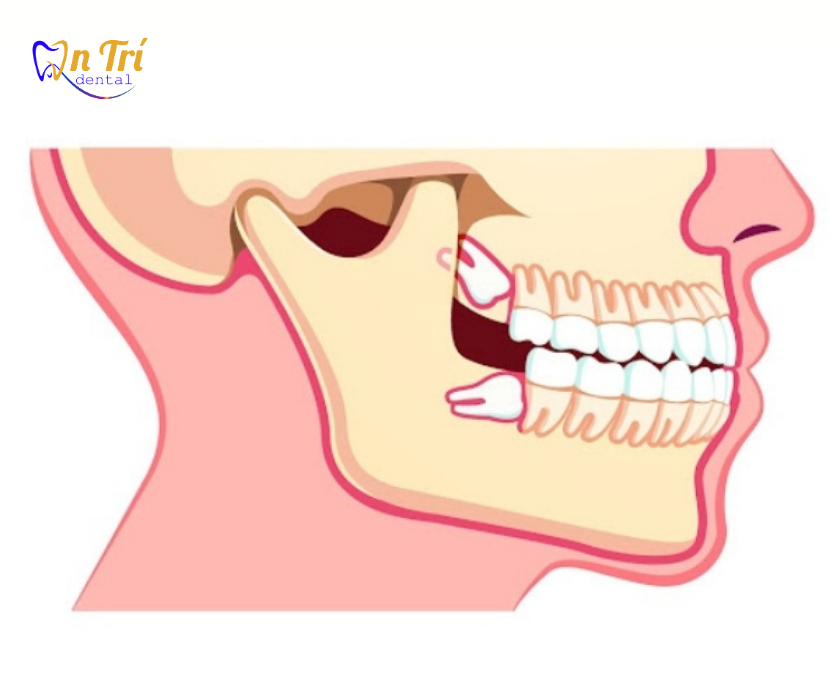

Răng khôn mọc lệch là gì? Vì sao lại đâm vào răng số 7?

Răng khôn là chiếc răng mọc cuối cùng trong cung hàm, thường xuất hiện từ 17–25 tuổi. Do không gian hàm đã gần như kín chỗ, răng khôn dễ mọc lệch hoặc bị kẹt trong xương hàm.

Khi răng khôn mọc lệch theo hướng nghiêng về phía trước, phần thân hoặc chân răng sẽ tì trực tiếp vào răng số 7 (răng cối lớn thứ hai). Áp lực này không chỉ gây đau nhức mà còn làm hỏng cấu trúc răng số 7, thậm chí gây tiêu xương.